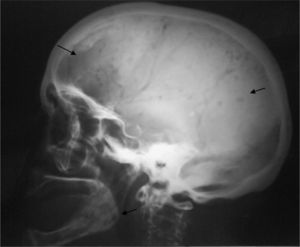

En la radiología simple se evidenciaron lesiones osteolíticas, sin bordes esclerosos de distintos tamaños y sin destrucción cortical en fémures (fig. 1), húmeros (fig. 2), parrilla costal, clavículas y cráneo (fig. 3), sin captación gammagráfica (Tc99) de las mismas.

Ante el diagnóstico diferencial de dichas lesiones (mieloma múltiple, metástasis de carcinoma de mama, pulmón, riñón y tiroides, enfermedad granulomatosa, mastocitosis, enfermedad de Gaucher) se realizó un aspirado de médula ósea que mostró una infiltración por células plasmáticas dismórficas del 23% y permitió confirmar el diagnóstico de MM no secretor (tabla 1).